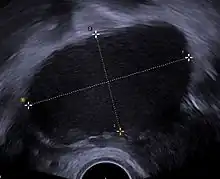

A health history and a physical examination can lead the health care practitioner to suspect endometriosis. There is a clear benefit for performing a transvaginal ultrasound (TVUS) as a first step of testing for endometriosis.[99]

Ultrasound

Vaginal ultrasound can be used to diagnosis endometriosis, or for localizing endometrioma before surgery.[117] This can be used to identify the spread of disease in individuals with well-established clinical suspicion of endometriosis.[117] Vaginal ultrasound is inexpensive, easily accessible, has no contraindications and requires no preparation.[117] By extending the ultrasound assessment into the posterior and anterior pelvic compartments a sonographer is able to evaluate structural mobility and look for deep infiltrating endometriotic nodules.[118] Better sonographic detection of deep infiltrating endometriosis could reduce the number of diagnostic laparoscopies, as well as guide disease management and enhance patient quality of life.[118]